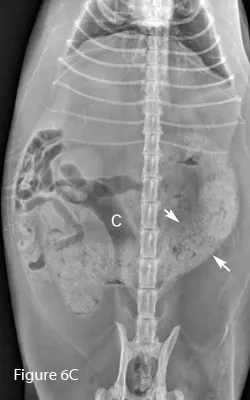

Lateral (Figure 6B) and ventrodorsal (Figure 6C) abdominal radiographs of severely distended segment of bowel identified sonographically and properly diagnosed as severe small intestinal obstruction (arrows). Of note, there is fecal-like material in the small intestine. An ileocecocolic mass was diagnosed during exploratory laparotomy. This mass was apparently obscured by gas during ultrasound examination. (C = colon)